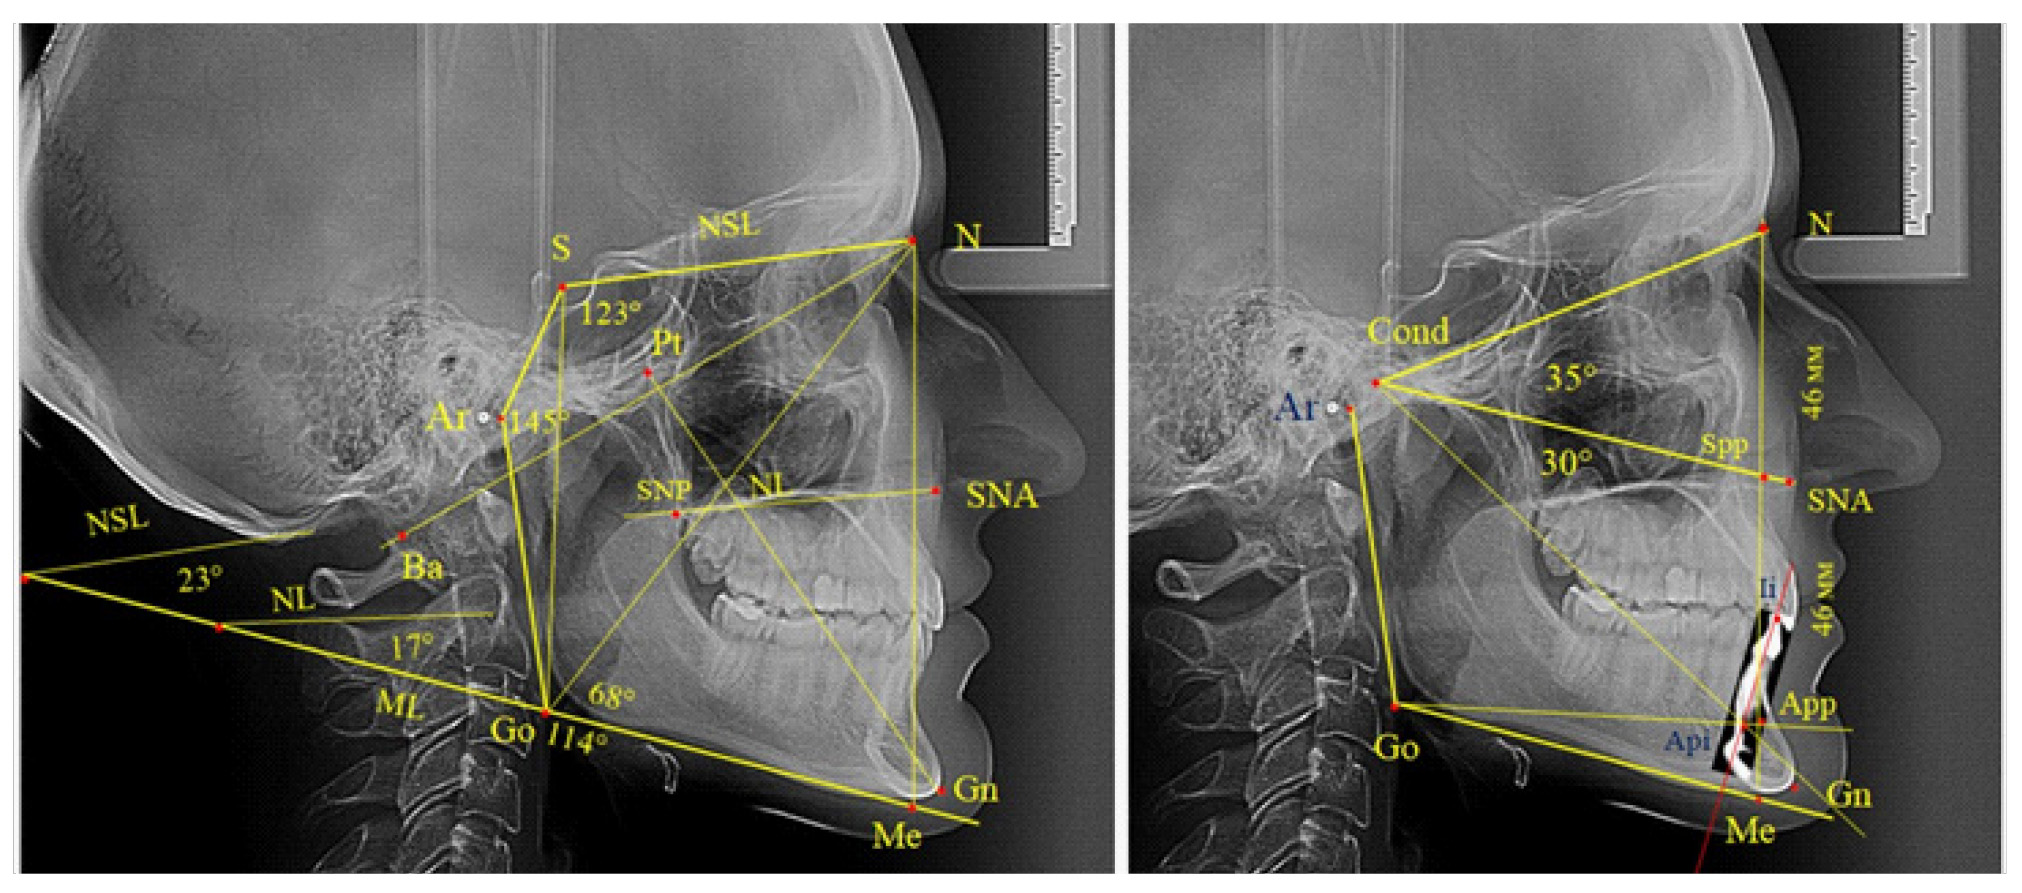

Полученные данные позволили разработать рабочую схему для определения физиологических и патологических вариантов роста лица (рис. 2).

Рис. 2. Рабочая схема дифференциальной диагностики физиологических и патологических вариантов роста лица